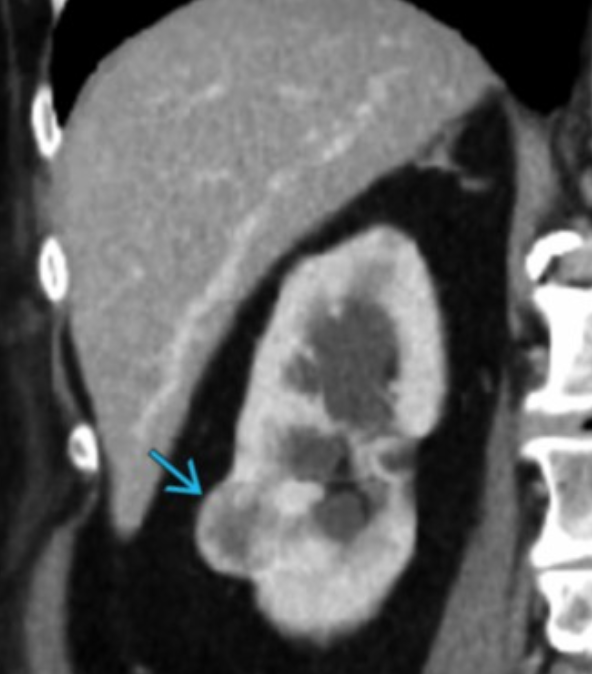

Xanthogranulomatous Pyelonephritis

RCC